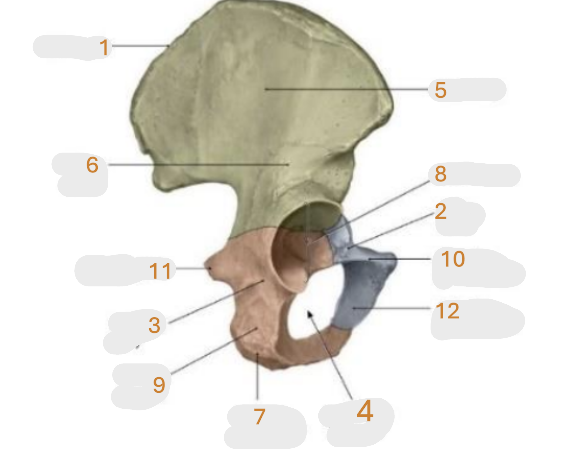

Where is the iliac crest

1

Where is the pubis body

2

Where is the ischium body

3

Where is the obturator foramen

4

Where is iliac wing

5

Where is the ilium body

6

Where is the ischial tuberosity

7

Where is the acetabulum

8

ischial ramus

9

Where is the superior pubic ramus

10

Where is the ischial spine

11

Where is the inferior pubic ramus

12